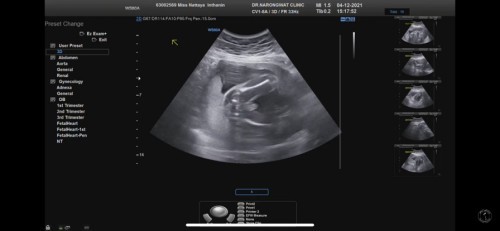

เค้าว่าชายค่ะ ลักษณะท้องกับสะดือไม่สามารถบอกเพศได้นะคะแม่ น้องมีจู๋นะค้าาา😆

จู๋ชัดมากเลยค่ะแม่ บ้านนี้ก็แบบนี้เลย

ชายค่ะแม่ เห็นจู๋ชัดเลย

เห็นเหมือนมีกระจู๋☺️